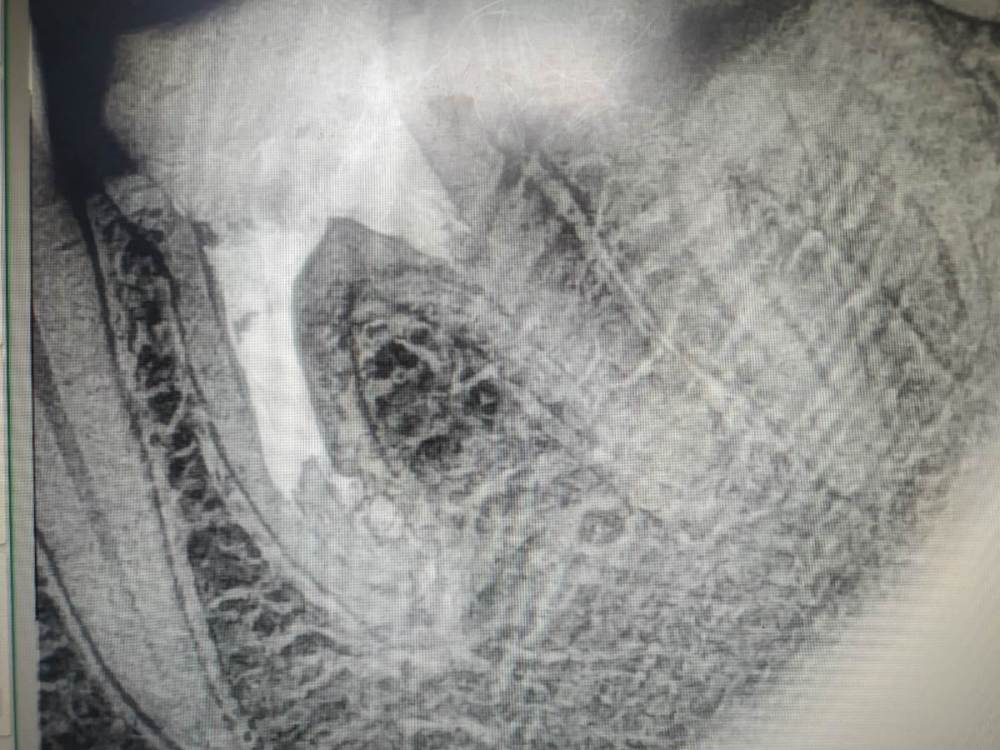

это да, но бывает, это устье раздваивается далеко не в устьевой части корня,а глубоко в средней , например как тут, хз как туда попасть

post-56770-0-48666200-1582799105_thumb.jpg

мое мнение(человека без микро), в этом случае нужно просто работать в ванночке из ГХ, он растворяет пульпу, а вовремя пломбировки это ответвление  заполнится силером.

Ничего не запомлнится,к сожалению, если не обработать механически.Измеряете на снимке расстояние до разветвления-стопер на файле 08 ставите так же и гнете кончик файла язычно,либо вестибулярного. Потихоньку тыкаемся и поворачивает,тыкаемся и поворачивает файл(подобно байпасу)нашли один канал-берете следующий 08,не вытаскивая первый и повторяет действия